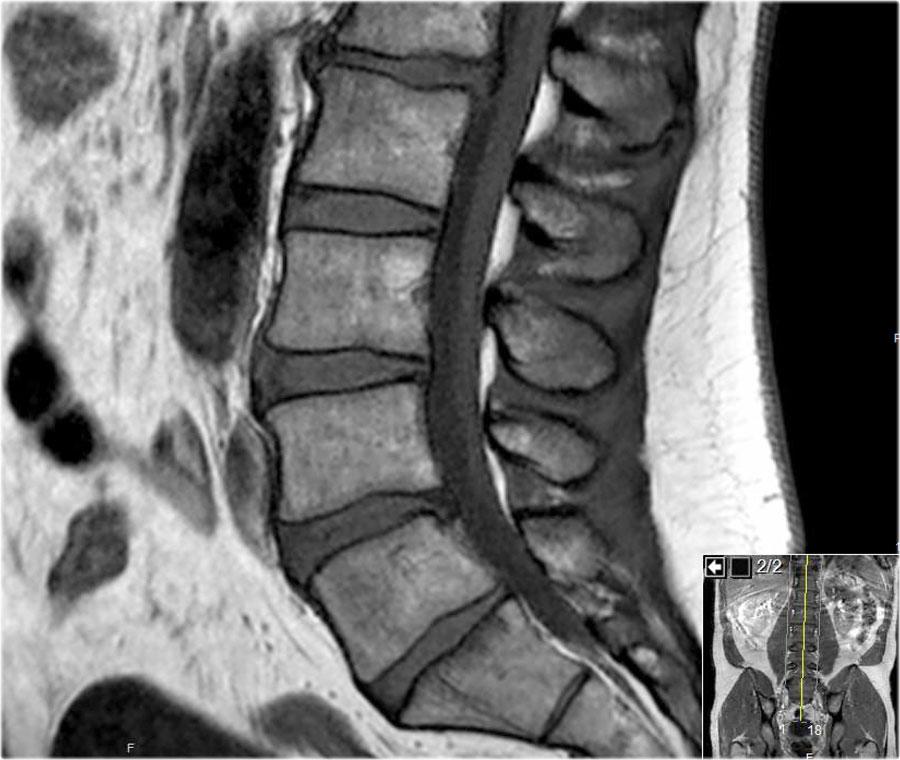

Trước tiên hãy cuộn qua các hình ảnh chuỗi xung T1W mặt phẳng đứng dọc này.

Các dấu hiệu là gì?

Sau đó tiếp tục xem chuỗi ảnh tiếp theo.